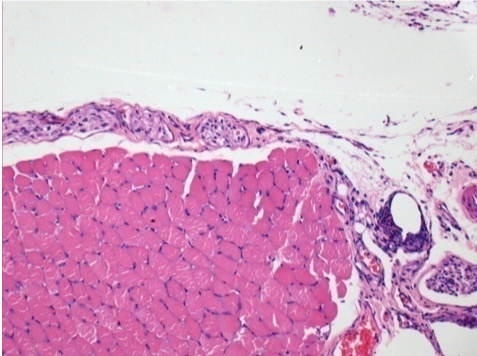

0.5 ml ( 5x 0.1ml) Endopeel SC Injection in the right subcutaneous pretibial area.

L:200x-Control-SC

R-D10-SC-200X